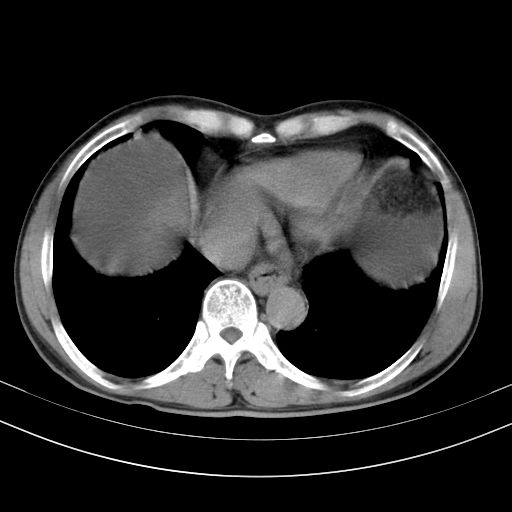

以下是引用随光逐影在2010-2-28 10:23:00的发言:[br]1)考虑肝癌;建议行ct增强扫描检查。2)肝硬化,脾大,腹水。3)慢性胆囊炎。